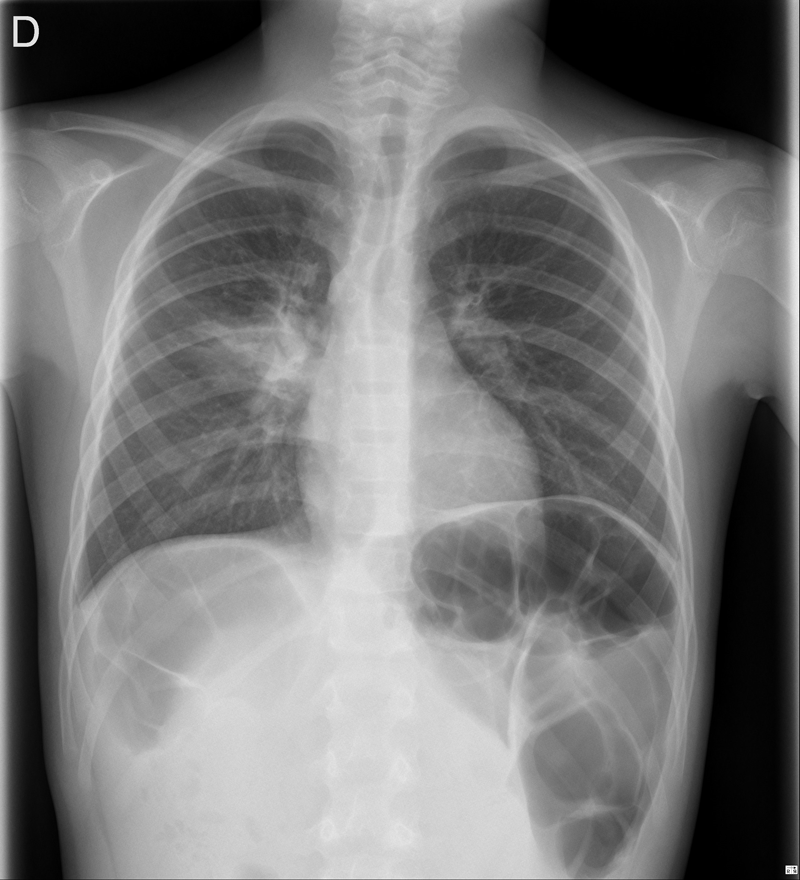

Niño de 9 años que acude a Urgencias por fiebre de hasta 38,9 °C de 72 horas de evolución asociada a tos productiva y mucosidad nasal. En la auscultación pulmonar se aprecian crepitantes en el campo superior derecho. El resto de la exploración física es normal. Se realiza radiografía de tórax posteroanterior, única proyección, que evidencia un aumento de la densidad en el campo pulmonar superior derecho, pero hay algo más.